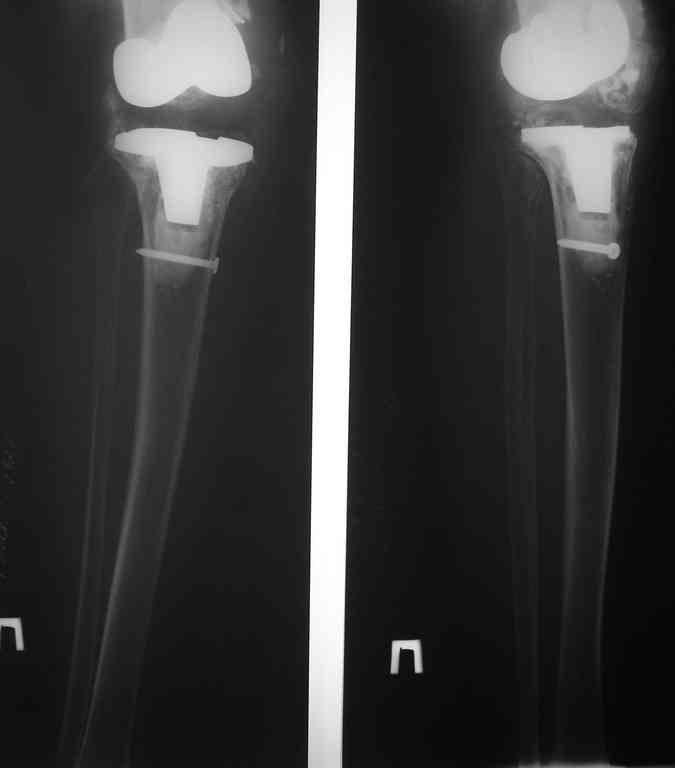

This patient is a 78 y o woman, she has osteoarthritis.3 years ago she had a total right knee replacement (Zimmer LPC).

after she started towalk without a cane,she felt that her knee is (giving way).the clinical knee examination showed medial knee instability and valgus deformation of this knee.2 years ago MCL repair was achieved……and no improvement.A year ago,she had knee replacement for this knee for the second time with bigger-sized implant and no improvement…now she using crutches and knee orthosis. In attachments ,2 monthes ago x-ray images.Any suggestion?